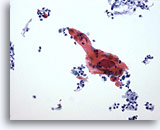

Figure 83

Bronchial wash

A pearl of keratinized cells from a case of squamous cell carcinoma.

60x

Bronchial wash

A pearl of keratinized cells from a case of squamous cell carcinoma.

60x